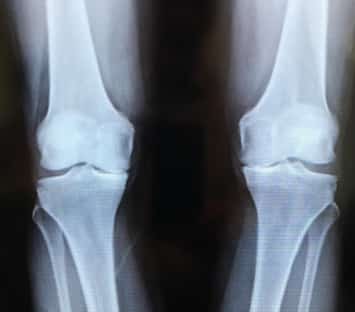

February 2017

September 2017